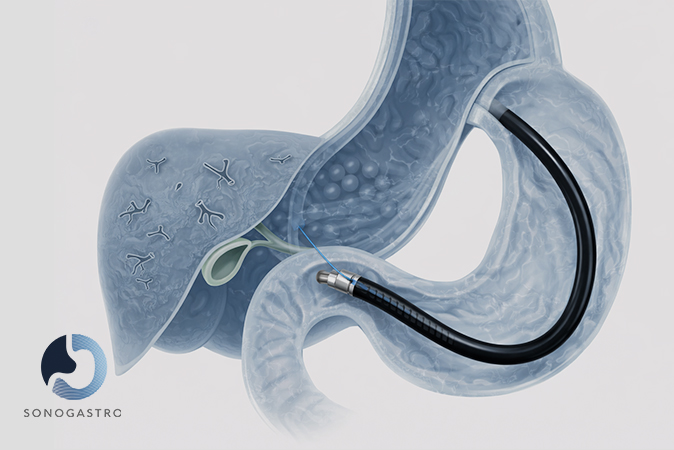

Endoscopic ultrasound (EUS) for pancreatic, biliary, and gastrointestinal conditions.

Guided endoscopic tissue sampling when clinically justified.

Hepatobiliary

Conditions

Fatty liver disease

Elevated liver enzymes

Gallstones and biliary disorders

Pancreatic cysts or lesions

Pancreatitis

Cirrhosis

Hepatitis (viral or non-viral)

Cholecystitis